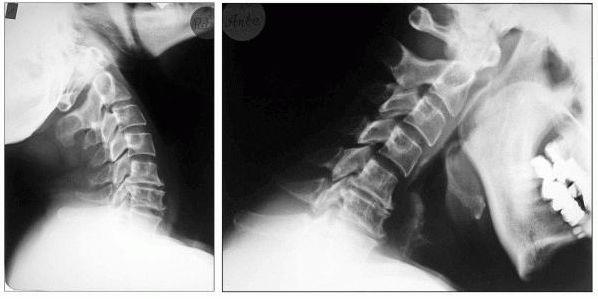

Die Myelograhie dient der speziellen Darstellung des Wirbelkanals im Röntgen-Bild. Dazu wird zunächst durch Lumbalpunktion ein wasserlösliches Kontrastmittel in den Wirbelkanal eingebracht. Die Untersuchung wird bei besonderen Fragestellungen betreffs raumfordernder Prozesse des Spinalkanals, oder bei der Diagnostik ausgeprägter degenerativer Veränderungen im Bereich von Hals- oder Lendenwirbelsäule eingesetzt.

Wörtlich übersetzt: Rückenmarkserkrankung. Meistens tritt sie in Zusammenhang mit einer Rückenkanalsstenose im Halsbereich auf, dann wird sie als cervikale Myelopathie bezeichnet. Sie geht mit Gangstörung (das Gehirn erhält keine Lageempfindungen mehr), Gefühlsstörungen, Lähmungen und Spastik einher.

Im Bereich der Halswirbelsäule kann es dadurch zu Druck auf das Rückenmark kommen (siehe cervikale Myelopathie)